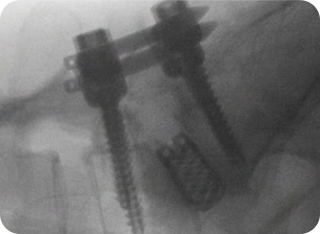

내시경 유합술 사진1

내시경 유합술 사진2

3

내시경 유합술

척추 불안정성이 심한 경우, 내시경을 통해 병변 부위를 고정·융합하는 수술입니다.

기존 개방형 유합술보다 절개 범위가 작아 합병증 위험이 낮고,

척추 안정성을 확보할 수 있습니다.

• #척추 불안정증

• #심한 퇴행성 척추질환

• #재발성 디스크나 다발성 병변